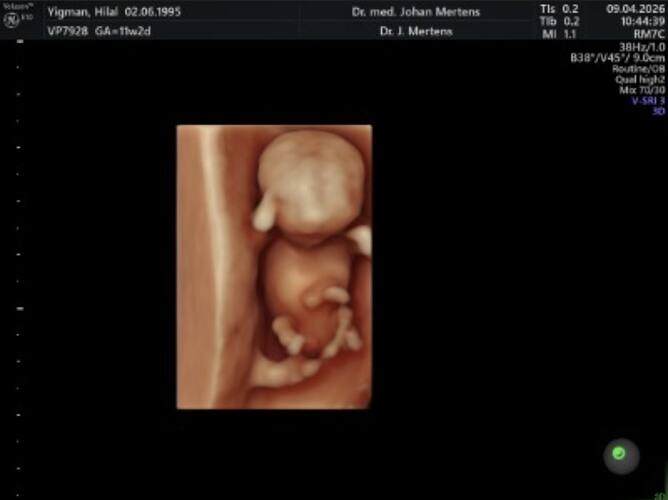

Erkek bebekler daha mı erken gosteriyor benim doktorum 11.haftada tahmin etmişti 14 de net soylemisti @Leyla1991

Bilemiyorum ama bebekten bebeğe değişiyor olabilir bende 11 haftalıkken ikili teste öğrendim cinsiyetini 3 gebeligimi ve hatta yanlışdir diye kontrol zamanı kendi Dr sormuştum oda doğru demişti